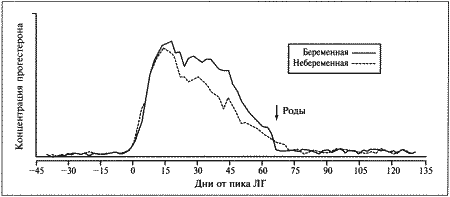

Фиг. 1.2.

Динамика концентрации прогестерона в плазме крови на протяжении эстрального цикла. Составлено на основании данных, полученных при наблюдении за 8 собаками. За точку отсчета принят овуляторный пик ЛГ. Ключевые показатели, используемые для идентификации стадии цикла и вычисления фертильного периода (см. текст): концентрация прогестерона в конце анэструса находится на базальном уровне (может не выявляться) (х-х), затем в период проэструса незначительно повышается до определяемого уровня (о-о); в период, предшествующий овуляции, концентрация прогестерона возрастает одновременно с пиком ЛГ (+-+). За временной интервал между пиком ЛГ (▲-▲) и овуляцией уровень прогестерона повышается до характерных значений начала фертильного периода и продолжает увеличиваться (-•) приблизительно до 30 дня.

Данные о концентрации прогестерона в сыворотке крови могут служить ориентиром для определения фертильного периода у сук. Механизмы и динамика изменения концентрации прогестерона описаны в предыдущем разделе (фиг. 1.2).

В конце анэструса концентрация прогестерона в сыворотке крови находится на базальном уровне (и практически не определяется), к окончанию проэструса она повышается до низкой, но поддающейся определению отметки (около 3 нмоль/л или 1 нг/мл). И продолжает повышаться, достигая уровня 3–6 нмоль/л (1–2 нг/мл) к моменту овуляторного пика ЛГ; 2 дня спустя (в день овуляции) показатели достигают 6–12 нмоль/л (2–4 нг/мл), а к 4 дню (т. е. к началу фертильного периода) — 18–30 нмоль/л (6–10 нг/мл) (фиг. 1.1). Концентрацию прогестерона определяют в плазме крови, поскольку анализ других жидкостей (слюны и мочи) в настоящее время не дает точных результатов. Исследование проводят после появления первых признаков проэструса и повторяют по меньшей мере каждые 2–3 дня до окончания проэструса или начала поведенческого эструса. Такая методика позволяет выявлять стремительное нарастание концентрации прогестерона перед овуляцией и соответственно рассчитать дату возможной вязки. В случаях очень короткого проэструса исследование начинают раньше.

МЕТЭСТРУС

С начала метэструса концентрация прогестерона продолжает нарастать, достигая максимума (порядка 90–270 нмоль/л; 30–90 нг/мл) к 30 дню от пика ЛГ, а затем постепенно снижается до 30 нмоль/л (10 нг/мл) к 60 дню от пика ЛГ. Таким образом, концентрация прогестерона в крови сохраняется на уровне 30–90 нмоль/л (10–30 нг/мл) около 2 месяцев после окончания эструса; более низкий уровень указывает на ановуляторный цикл или дисфункцию желтых тел. Вплоть до 60 дня время и диапазон колебаний концентрации прогестерона у беременных и небеременных самок одинаковы. Различия проявляются в резком снижении концентрации прогестерона перед родами (см. ниже), тогда как у небеременных самок, у которых отсутствует лютеолитический механизм, концентрация прогестерона снижается постепенно и достигает 3–9 нмоль/л (1–3 нг/мл) в течение последующих 30–60 дней. Неизвестно, проявляется ли активность желтых тел в строго запрограммированный отрезок времени или спад активности объясняется снижением лютеотрофической поддержки.

Роды

Снижение концентрации прогестерона перед родами наблюдается у большинства домашних животных и объясняется угнетением у беременной самки надпочечниковой секреции стероидных гормонов, что приводит к выработке эстрогена и простагландина эндометрием. У сук родам предшествует резкое падение концентрации прогестерона с 30 нмоль/л (10 нг/мл) до < 6 нмоль/л (< 2 нг/мл) в плазме крови; это, как сейчас принято считать, играет роль пускового механизма родов. Данный факт подтверждается и тем, что назначение прогестерона вызывает задержку родов, а препараты (например, эпостан), блокирующие его секрецию, — стимуляцию.

Резкое снижение концентрации прогестерона служит индикатором приближения родов. Концентрация > 6 нмоль/л (> 2 нг/мл) свидетельствует о том, что роды не начнутся в ближайшие 14 часов.

Эндокринные тесты на беременность

Как указано выше, пик концентрации прогестерона наблюдается приблизительно на 30 день, после чего она постепенно уменьшается, достигая к концу беременности 30 нмоль/л (10 нг/мл). Градиент снижения концентрации прогестерона после 30 дня у беременных сук практически такой же, как у небеременных. Понятно, что измерение концентрации этого гормона в целях диагностики беременности не имеет смысла.